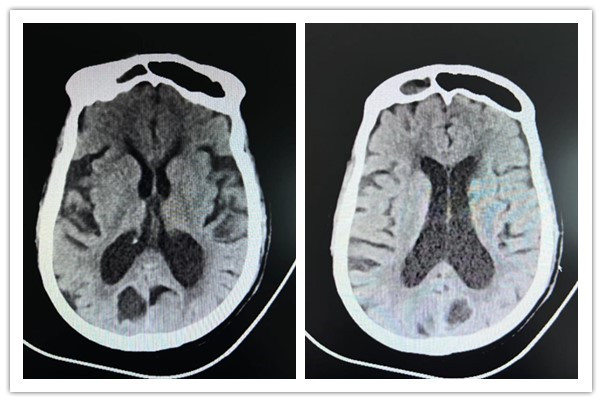

23點(diǎn)28分,醫(yī)學(xué)影像科立即為張女士進(jìn)行頭顱CT檢查,CT提示未見明顯出血,NIHSS評(píng)分22分,血常規(guī)、凝血系列未見明顯異常。束坤主治醫(yī)師評(píng)估張女士符合靜脈溶栓指征,與家屬進(jìn)行溶栓談話后,家屬同意靜脈溶栓治療并簽字,請(qǐng)示趙宇杰副主任醫(yī)師后予以溶栓治療。

0點(diǎn)24分,張女士在灃東院區(qū)腦病病區(qū)進(jìn)行阿替輔酶靜脈溶栓,DNT時(shí)間35分鐘。1點(diǎn)30分,溶栓治療結(jié)束,患者無明顯不適,生命體征平穩(wěn),NIHSS評(píng)分6分,完善顱腦DWI、MRA,溶栓治療成功。